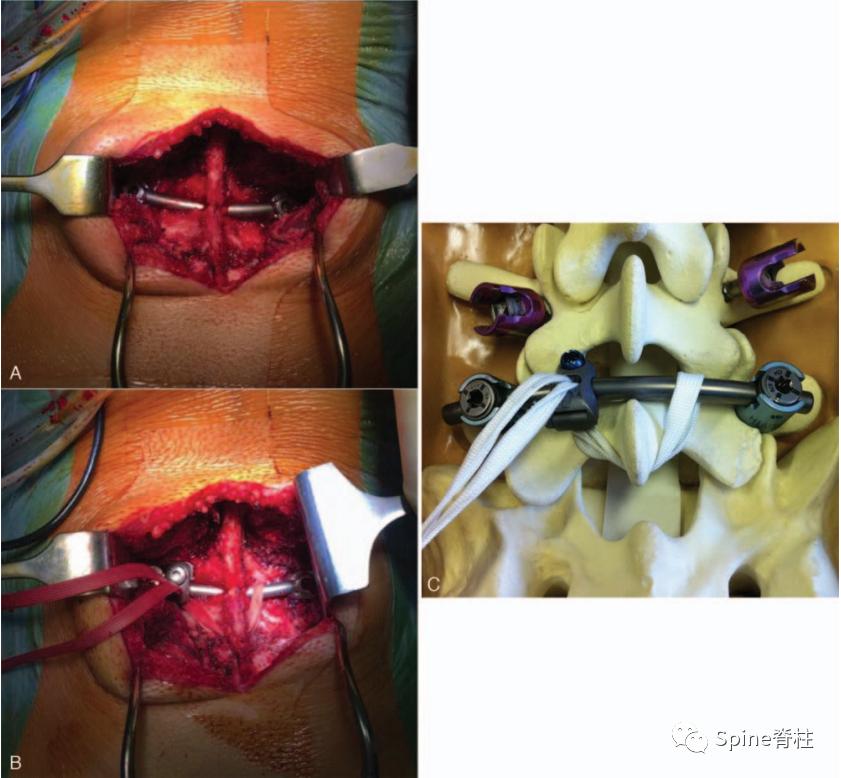

Berjano等2020年提出椎弓根螺钉-棒-张力带固定法(Screw-Rod-Band technique),是Scott接线法技术的改良。

7. 解剖型钉钩椎弓根螺钉系统

2022年,解放军总医院第三医学中心彭宝淦(我的硕导和博士后合作导师)和李端明主任提出了一种新型解剖型钉钩椎弓根螺钉系统。根据腰椎解剖,棘突与椎板成一定角度,椎板向后向上倾斜,椎板下缘和椎弓根螺钉尾部与矢状面成一定角度。根据上述解剖特征,解剖型钉钩椎弓根螺钉系统的钩和棒在这三个方向上都是倾斜的。钩棒与椎板完全匹配,有利于将钉钩安装在椎板的下缘,且易于将棒与万能椎弓根螺钉连接。此外,该系统可通过肌间隙入路置入。

PMID: 35979102